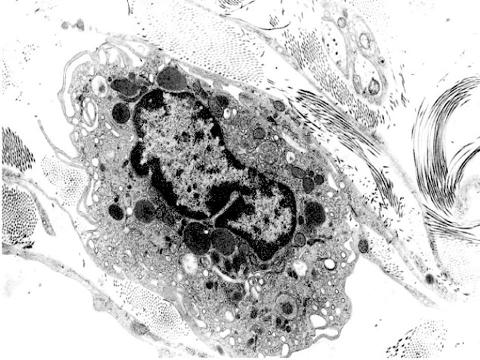

lisosomas. ME